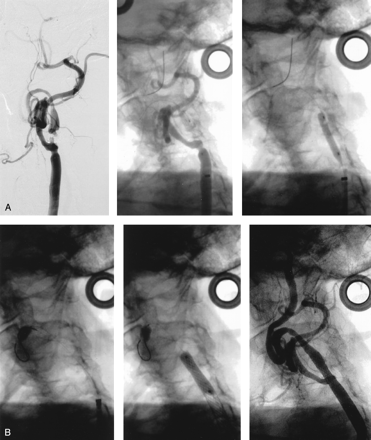

A and B, Illustration of the buddy catheter technique in a 70-year-old man.

A, Left, Left carotid angiogram shows near occlusion of the ICA. The 90° takeoff angulation made advancement of the GuardWire temporary occlusion catheter into the stenotic ICA impossible. Right, Angiogram shows the buddy catheter (5F, 125-cm JR4, arrow) positioned through a 6F guiding sheath, with its tip pointing into the angulated ICA lesion. The temporary occlusion catheter is advanced through the stenosis into the distal segment of the ICA.

B, Left, Angiogram shows that the inflated balloon of the temporary occlusion catheter is occluding the ICA. Right, Angiogram obtained after carotid artery stent placement. Two 10 × 30-mm Smart stents were deployed.

If the origin of the ICA is so severely angulated that the buddy wire strategy is unsuccessful, a “buddy catheter” system can be used to facilitate placement of the temporary occlusion catheter (Fig 4). An appropriately shaped, 5F, 125-cm-long catheter (eg, 4-cm curved right Judkin catheter [JR4], or an internal mammary artery catheter) is advanced through the guiding sheath and placed with its tip pointing into the ostium of the ICA. Then, through this catheter, the temporary occlusion catheter or a buddy wire is advanced through the stenosis into the ICA. The buddy catheter system can also be used to advance the temporary occlusion catheter through a very tight or fibrous stenosis. One has to remember that the temporary occlusion catheter or the buddy wire length has to be 300 cm when using this strategy. The buddy catheter is then removed over the wire, and the carotid artery stent placement procedure is carried out. The level of the ICA at which the occlusion balloon is inflated is of extreme importance. It should be at least 30 mm distal to the intended distal end of the stent. If this distance is not maintained, the stent delivery system can become imbedded into the temporary occlusion catheter system, with ensuing technical difficulties.